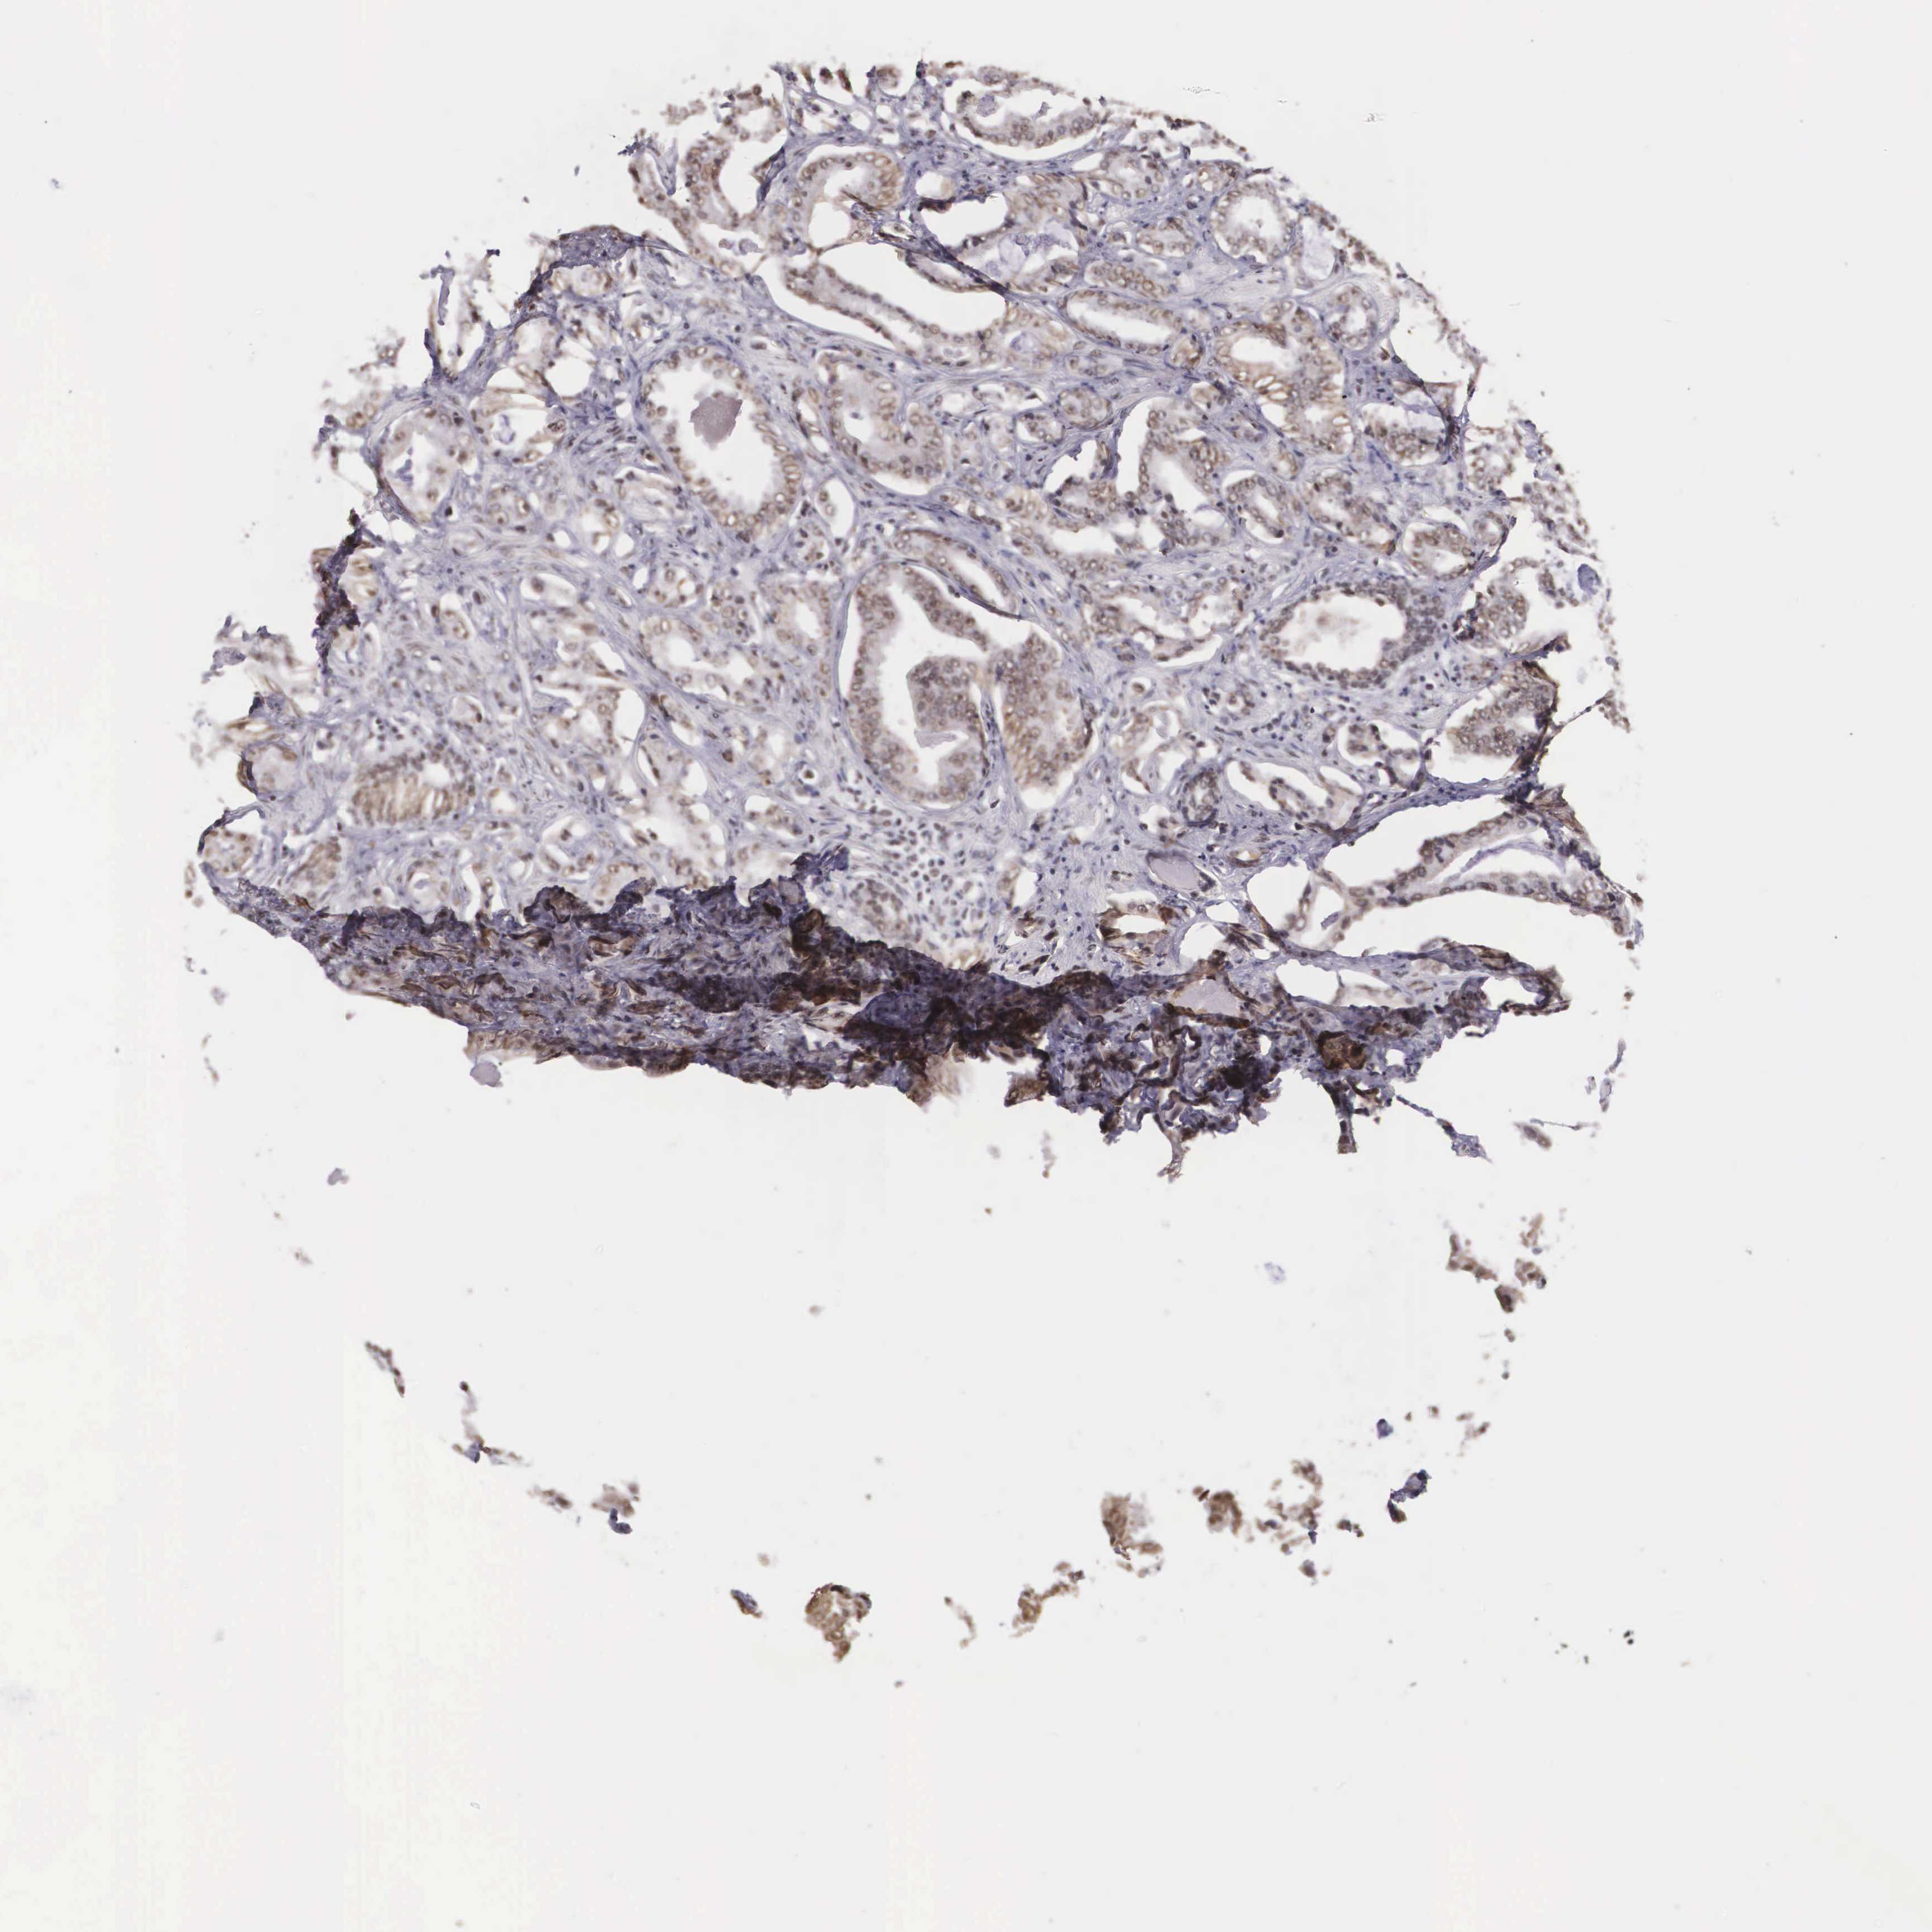

PROSTATE CANCER - Protein expressioni

A mouse-over function shows sample information and annotation data. Click on an image to view it in a full screen mode. Samples can be filtered based on level of antibody staining by selecting one or several of the following categories: high, medium, low and not detected. The assay and annotation is described here.

Antibody stainingi

Antibody staining in the annotated cell types in the current human tissue is reported as not detected, low, medium, or high, based on conventional immunohistochemistry profiling in selected tissues. This score is based on the combination of the staining intensity and fraction of stained cells.

Each image is clickable and will lead to virtual microscopy that enables deeper exploration of all samples and also displays staining intensity scores, fraction scores and subcellular localization as well as patient and tissue information for each sample.

Antibody CAB009882

Adenocarcinoma, Medium grade

Adenocarcinoma, Low grade

Adenocarcinoma, High grade